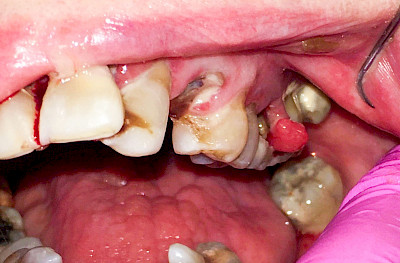

Schwellung mit Eiter: Abszess

Schwellungen im Zusammenhang mit akuten Entzündungen im Bereich der Zähne oder dem Zahnhalteapparat entstehen meist aufgrund schneller und starker Vermehrung von Bakterien sowie einer starken Abwehrreaktion des Körpers (Abszess). Diese Schwellungen entstehen meist in sehr kurzer Zeit – innerhalb von Stunden oder wenigen Tagen. Die Schwellungen sind sehr schmerzhaft. Nah am Zahnfleisch kann sich bei leichtem Druck auf die Schwellung Eiter entleeren. Mitunter fühlen sich die Menschen krank. In fortgeschrittenem Stadium kann auch Fieber auftreten. Hier ist sofort der Zahnarzt zu kontaktieren, um eine weitere Ausbreitung der Entzündung zu verhindern.